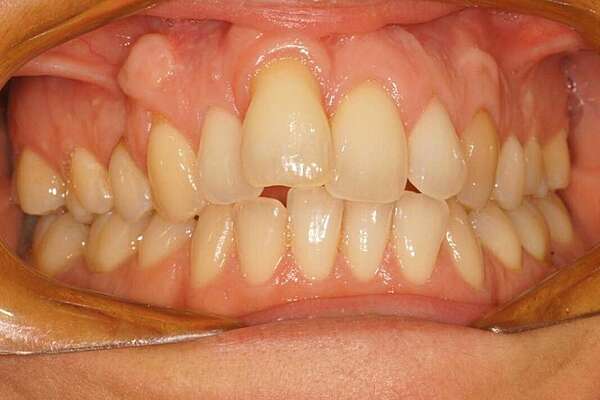

Important encombrement traité par gouttières